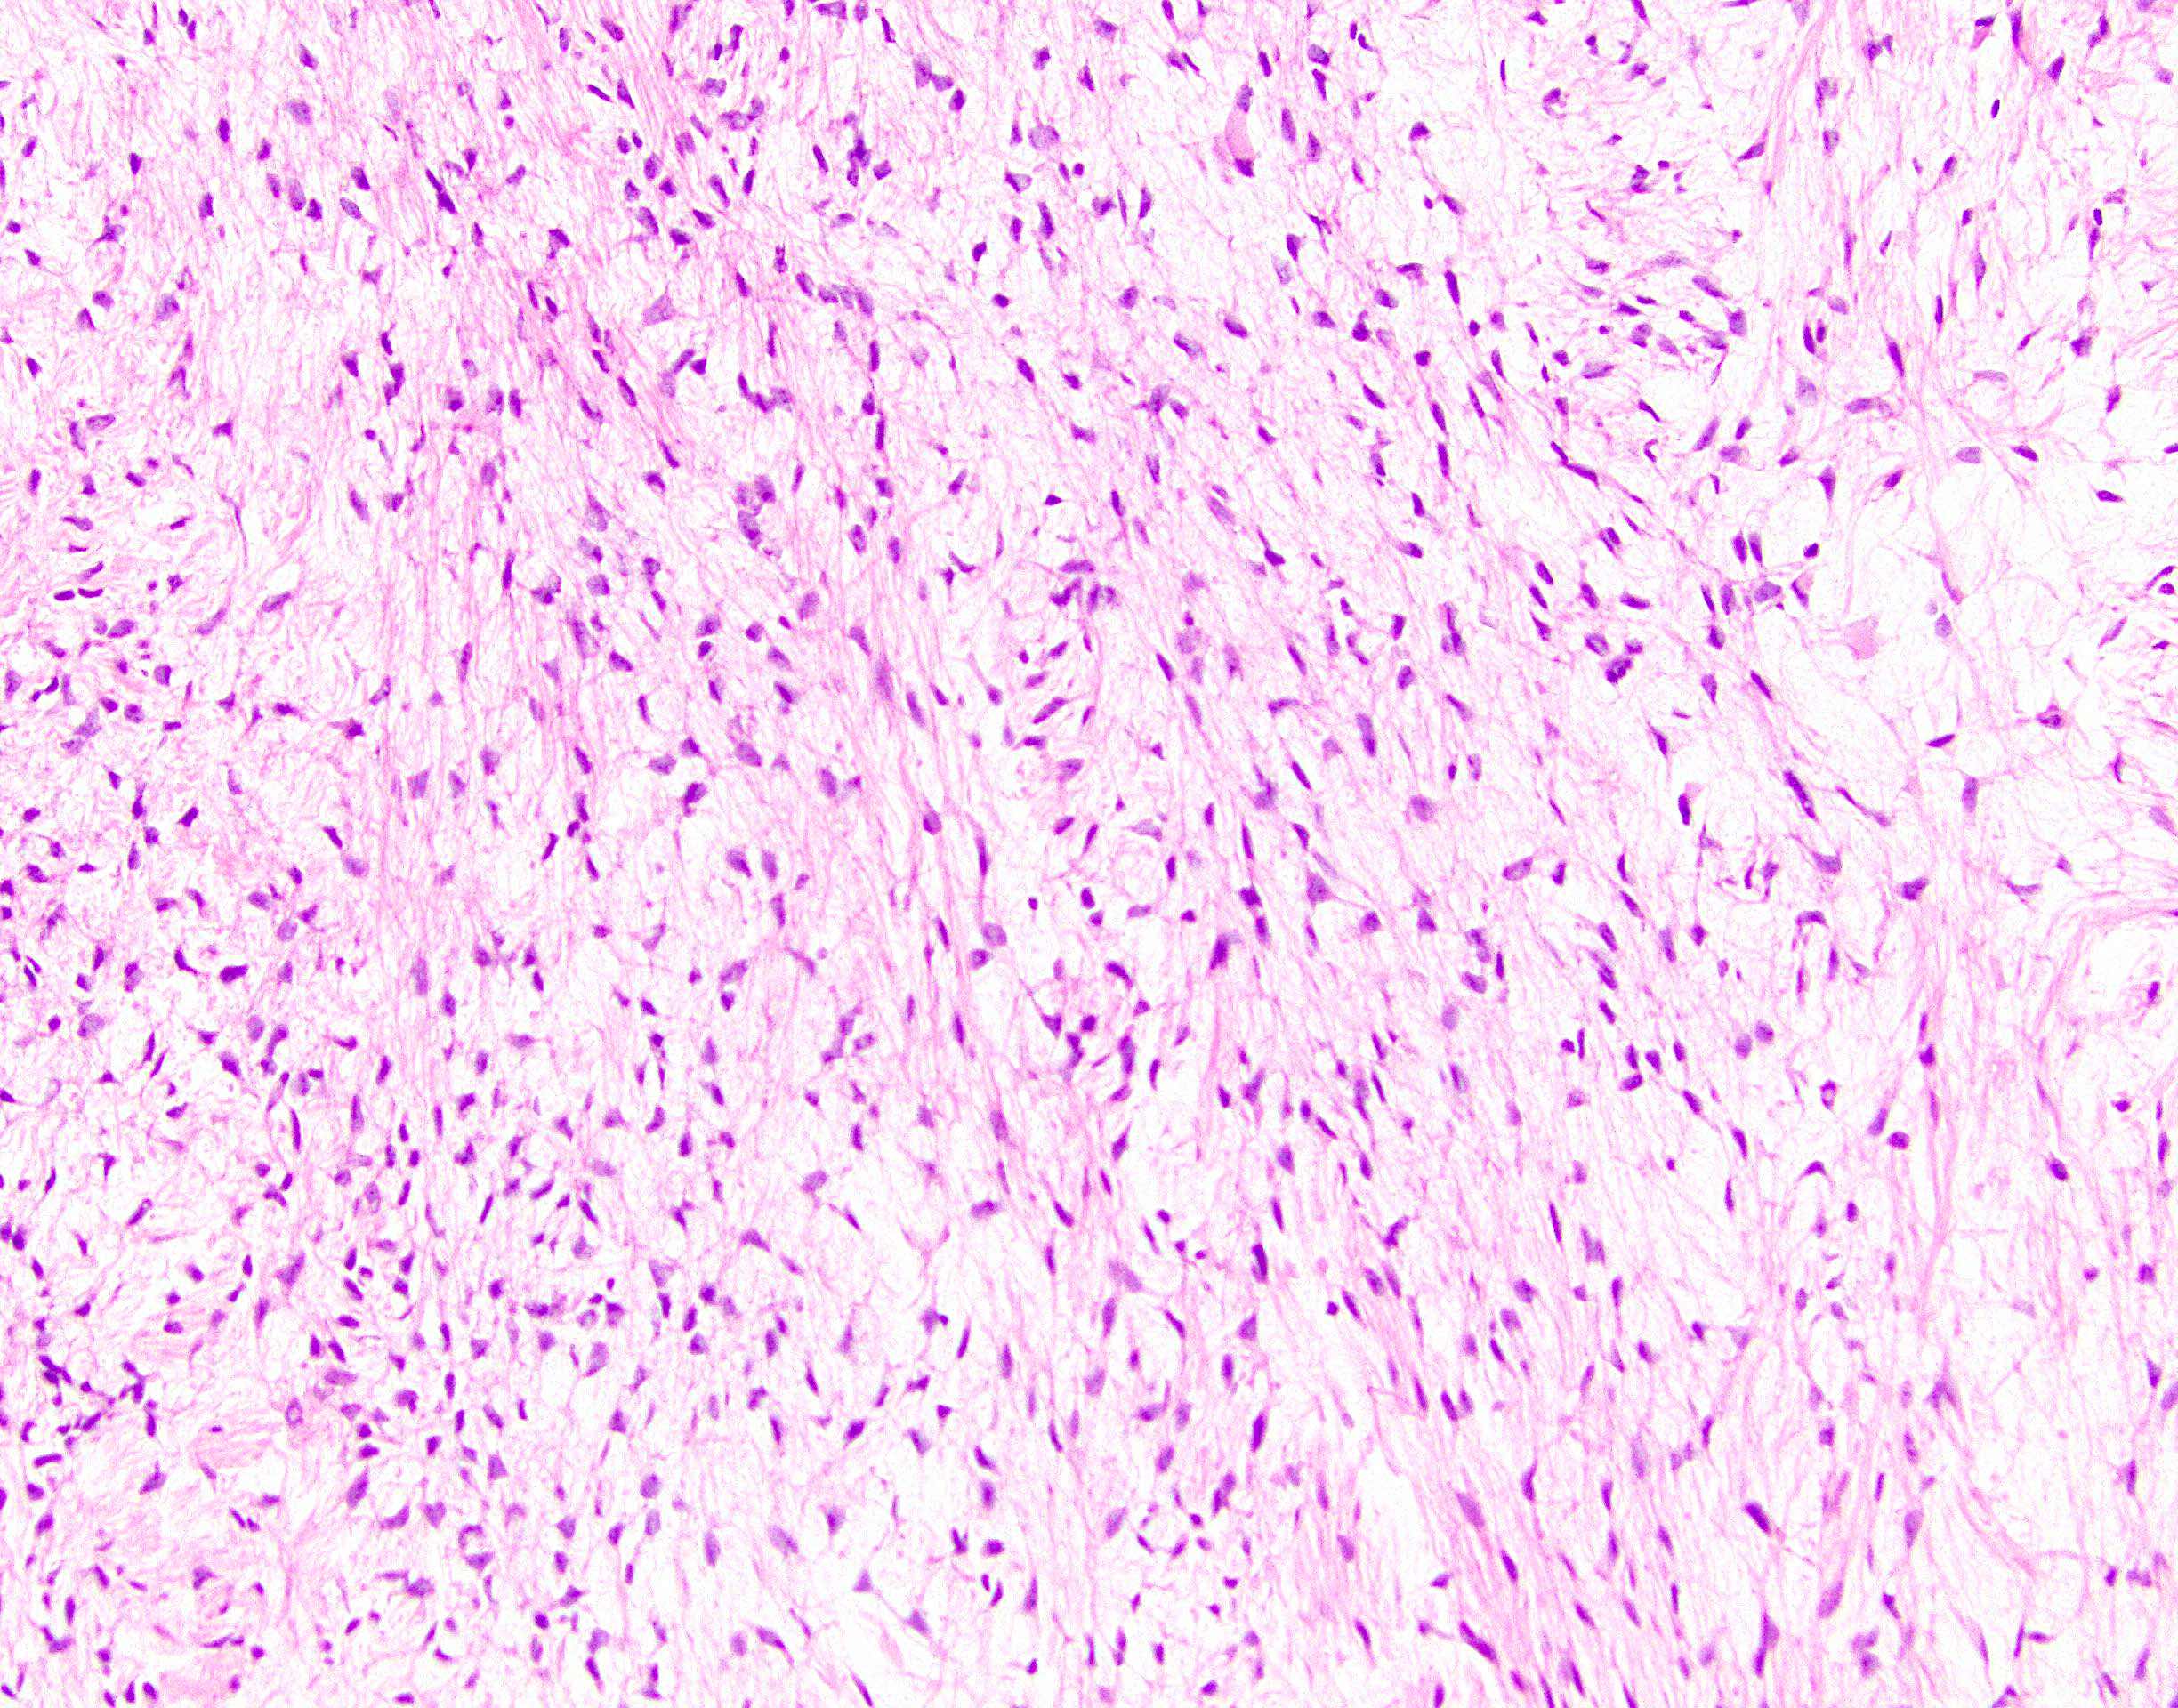

Microscopic (histologic) description

- Low to moderately cellular, bland fusiform or spindled cells with focal to diffuse whirling in heavily collagenized stroma with abrupt transition to myxoid areas

- 45% have epithelioid areas

- 40% contain poorly formed but large collagen rosettes

- Often infiltrates adjacent skeletal muscle

- Occasionally has areas of increased cellularity, atypia, necrosis or mitotic activity characteristic of intermediate to high grade sarcoma

- Recurrences may show increased cellularity and mitotic activity

Microscopic (histologic) images

- Cellular with spindle cells containing scant wispy cytoplasm, uniform elongated nuclei, small inconspicuous nucleoli

- Prominent myxoid background

- No significant nuclear pleomorphism or mitoses (Acta Cytol 2006;50:208, Cancer 1999;87:75)